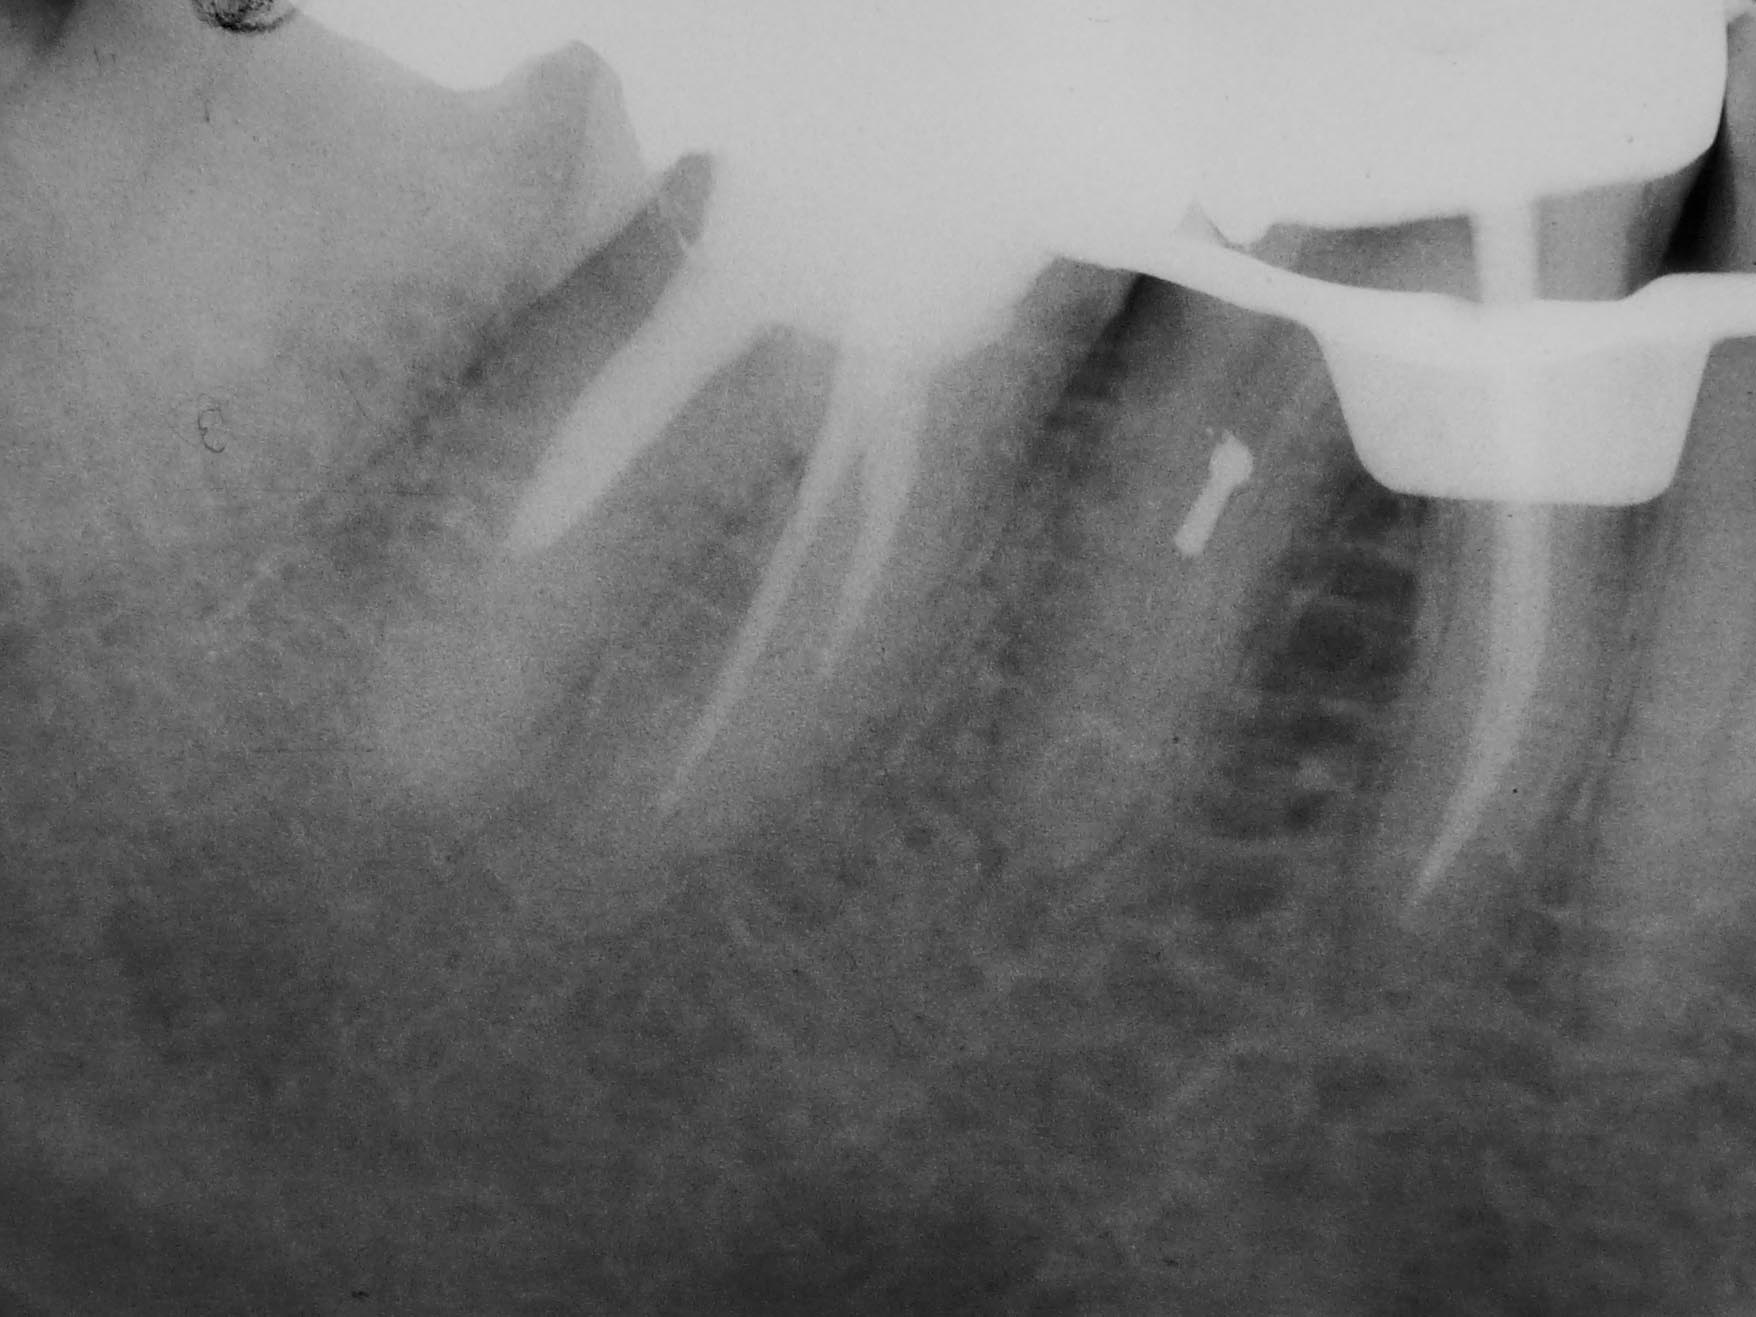

Rätselbild-2 Veröffentlicht 31. August 2009 am 1756 × 1317 in Shit happens: Das Rätselbild – Die Auflösung